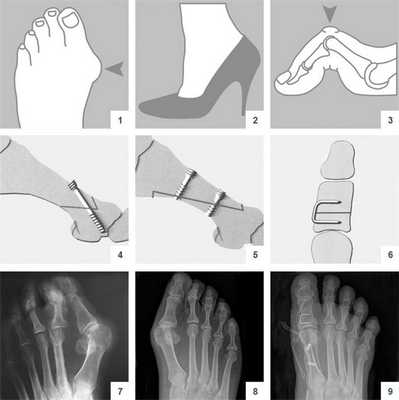

Виды операций на стопе

Операции, которые делают при вальгусной деформации, можно условно разделить на малоинвазивные и реконструктивные. Первые менее травматичны, однако эффективны только при экзостозах и начальной деформации. Малоинвазивные хирургические вмешательства выполняют через два-три прокола размером 3-4 мм.

Относится к миниинвазивным операциям. Во время хирургического вмешательства больным выполняют поперечную остеотомию через кожный разрез длиной 1 см. После этого дистальный костный фрагмент смещают в латеральном направлении и фиксируют с помощью специальной спицы.

CHEVRON

В ходе операции хирург выполняет V-образую остеотомию. Он перепиливает первую плюсневую кость в области головки, а костные фрагменты соединяет с помощью специальных титановых винтов. Поскольку фиксация очень прочная, в послеоперационном периоде пациент не нуждается в гипсовой иммобилизации.

Отметим, что Chevron-остеотомия эффективна только при незначительной деформации первого пальца стопы. В наше время в ортопедии ее используют все реже. Вместо нее большинство врачей делает Scarf-остеотомию.

SCARF

Z-образная остеотомия Scarf – это золотой стандарт лечения вальгусной деформации. Она позволяет установить головку плюсневой кости под нужным углом. В ходе хирургического вмешательства врачи также убирают деформацию суставной капсулы и меняют направление некоторых сухожилий.